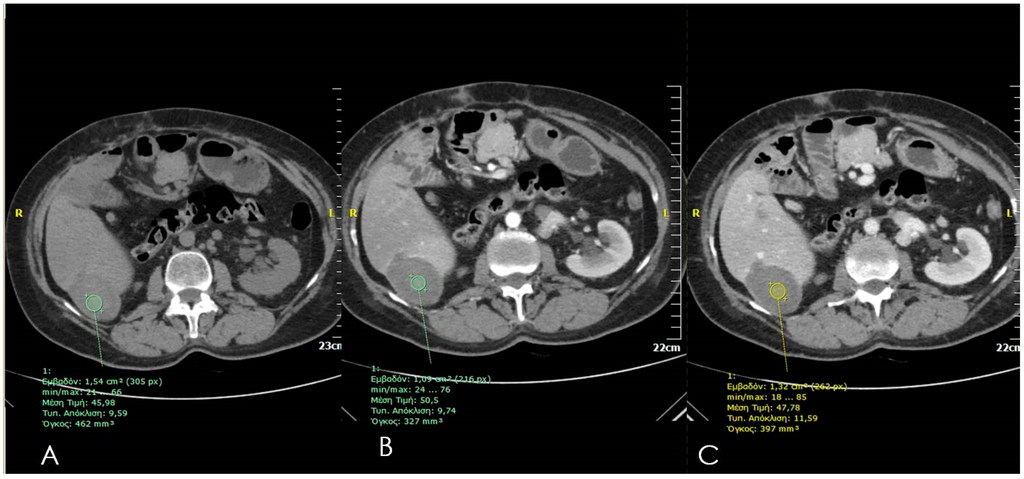

4. Computed Tomography (CT)